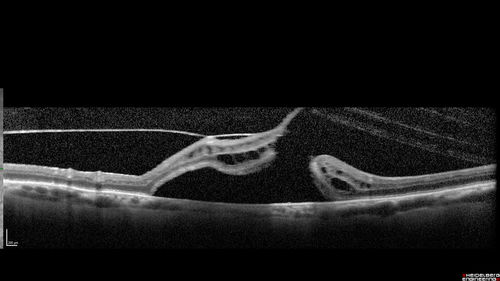

Macular Hole with Limited Retinal Detachment

87 year old female with decreased vision in the left eye for 2 months.  VA 5/200.  Initial three images are pre-op.  Then there is 3 months 6 months and 9 months post-op scans.  VA improved at 1 year to 20/50.  Surgery was done with Brilliant Blue.